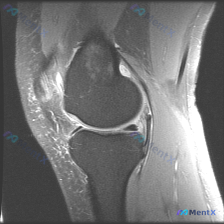

最近碰到一个有意思的读片病例:用户提供了一张膝关节MRI矢状位T1加权图像,主诉提示存在半月板异常,咱们一起来看看这个病例,整理一下思路。 病例核心信息 本次仅提供单张膝关节矢状位T1加权MRI,阅片可见: 1. 骨骼结构:股骨远端、胫骨近端骨皮质连续,骨髓信号符合正常脂肪信号分布,无局灶性异常低信...

刚看到这个膝关节MRI读片的病例,整理一下完整的病例信息和分析思路,和大家讨论一下这种情况的处理。 病例基础信息 本次提供的是单幅膝关节矢状位T1加权MRI影像,核心疑问是评估是否存在半月板异常。 影像学观察结果 我们先按解剖结构整理观察结果: 1. 骨骼结构:股骨远端、胫骨近端、髌骨骨皮质连续,骨...

看到一个很有代表性的读片病例,怀疑半月板异常但单张T1加权MRI没有发现明确问题,整理了分析思路和大家分享。 病例核心信息 问题:临床怀疑半月板异常,提供单张膝关节矢状位T1加权MRI,需要做影像观察和分析 影像系统性观察结果 1. 骨性结构:股骨远端、胫骨近端、髌骨轮廓规整,骨髓信号正常,未见骨质...

刚看到一份膝关节MRI单矢状位切面的读片需求,核心问题是观察半月板异常,我整理了完整的分析思路分享给大家。 一、病例基本影像信息 这是一张膝关节矢状位MRI影像,根据信号特征判断:不符合典型T1加权像(骨髓信号偏低,关节软骨、积液呈高信号),更符合质子密度加权像(PDWI)或T2加权像,这类序列对半...

刚整理了一份膝关节MRI读片病例,分享一下完整分析思路。 病例影像基本信息 这是一张膝关节MRI矢状位图像,用户提问是否存在半月板异常,我们来一步步分析: 影像基础评估结果 1. 骨骼与关节: 股骨远端、胫骨近端皮质连续,无明显骨折,无明显骨髓水肿、软骨下囊肿,关节间隙和对合关系基本正常 2. 关节...